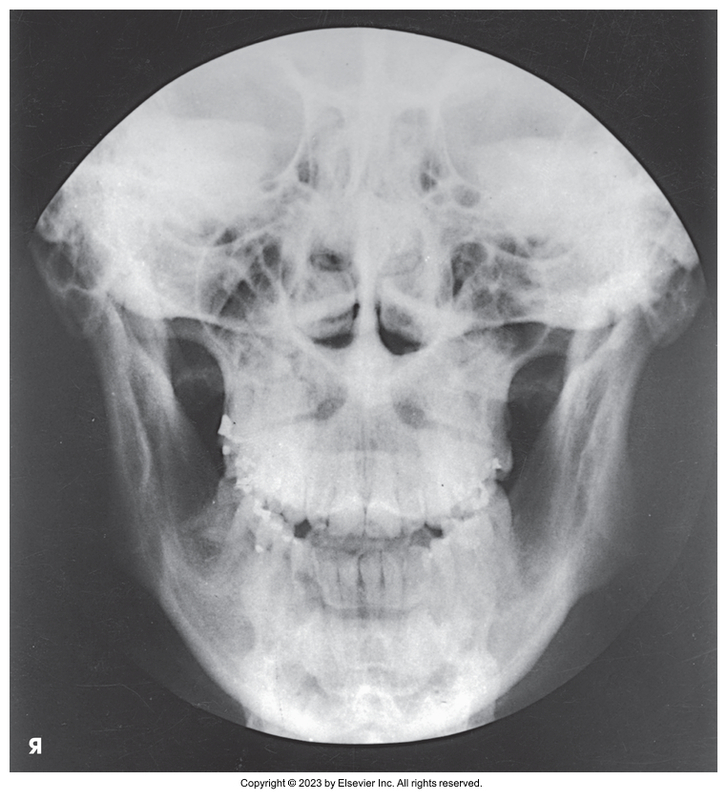

PA projection of skull

PA of skull